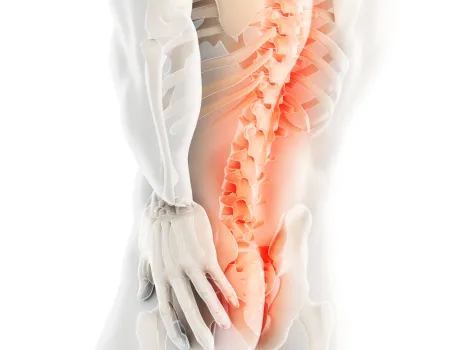

발은 우리 몸에서 건물의 주춧돌과 같은 역할을 합니다. 발의 틀어짐으로 인한 통증은 단순히 발의 문제로 그치지 않고 보행 패턴을 무너뜨리며 다리와 무릎 관절, 나아가 골반과 허리의 추간판까지 연쇄적인 영향을 미칩니다. 발의 문제를 조기에 발견해 치료하는 것이 전신 건강을 위해 중요합니다.

▲ 발의 문제로 인해 생기는 요통